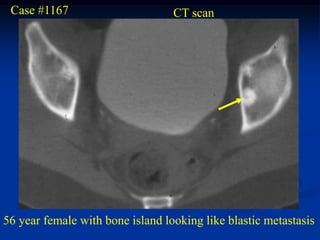

Case #1167                       CT scan

56 year female with bone island looking like blastic metastasis

Negative bone scan suggests a pseudotumor diagnosis